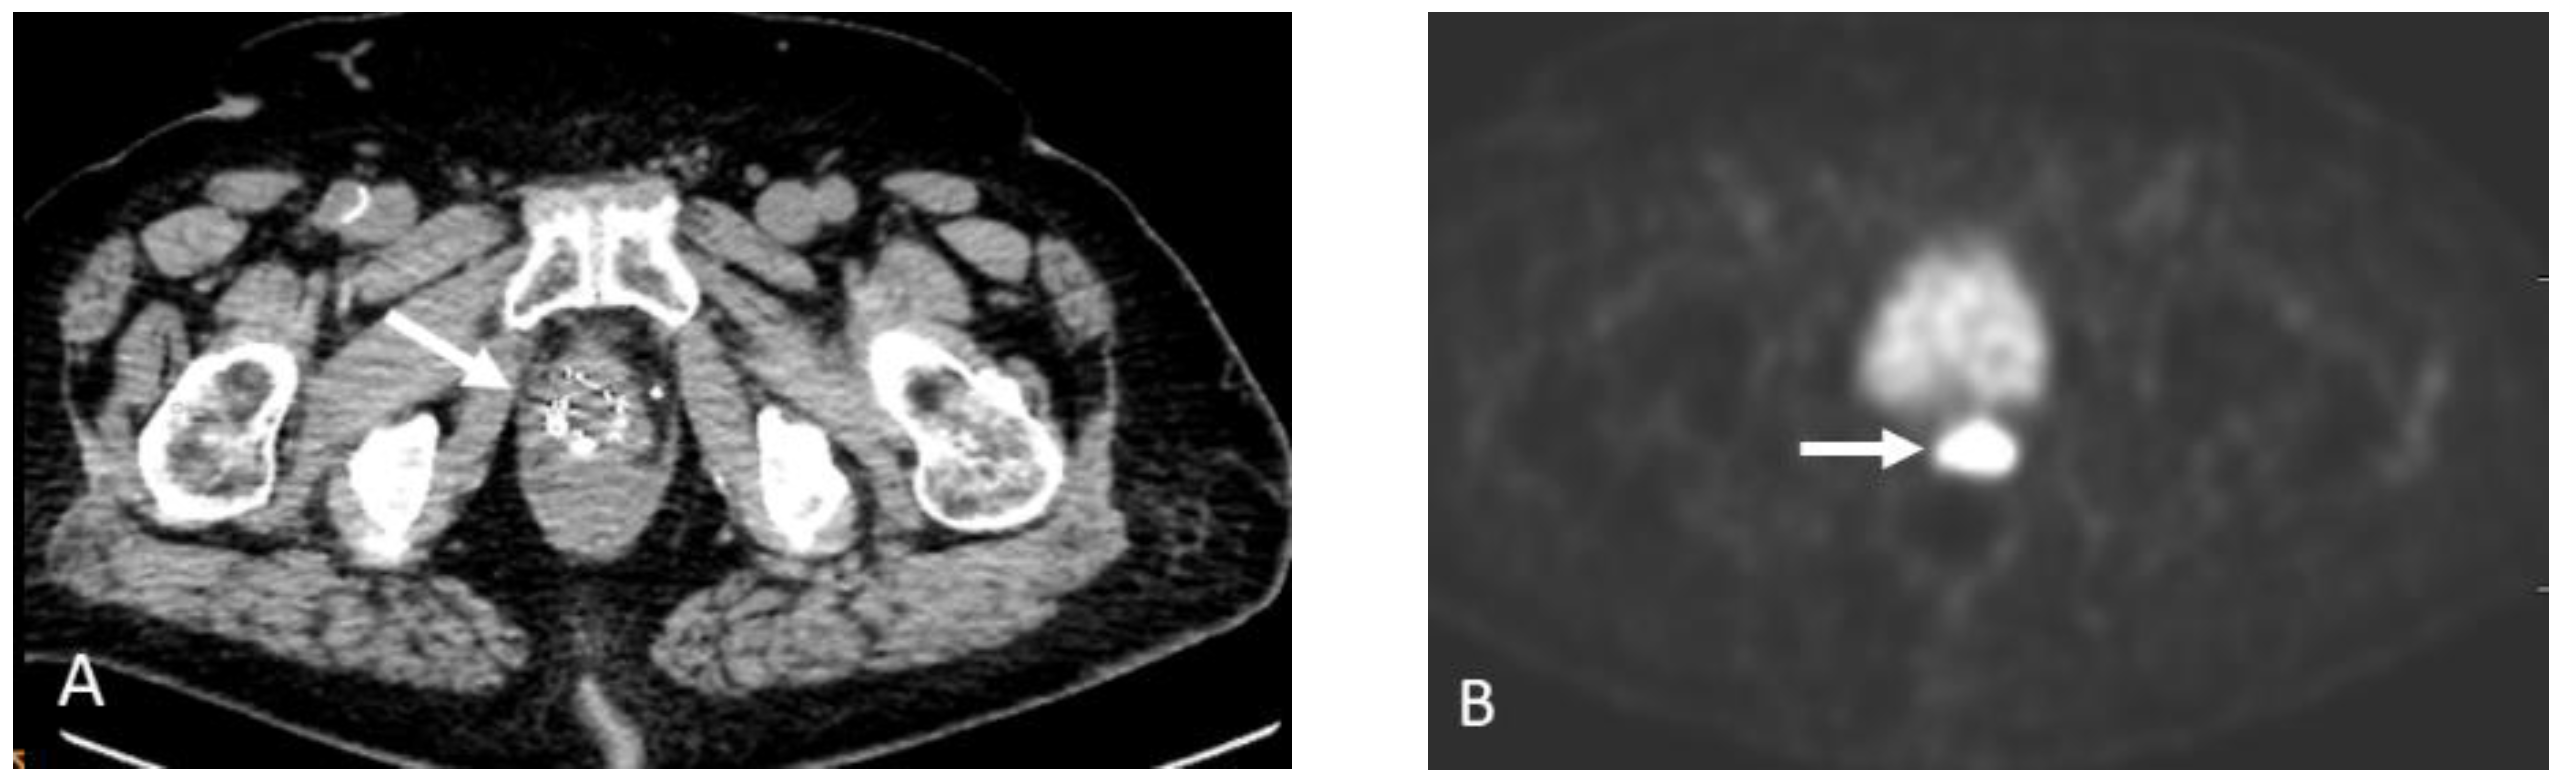

Detection of Loco-Regional Disease and Distant Metastases

1.9.3. Pearls and Pitfalls